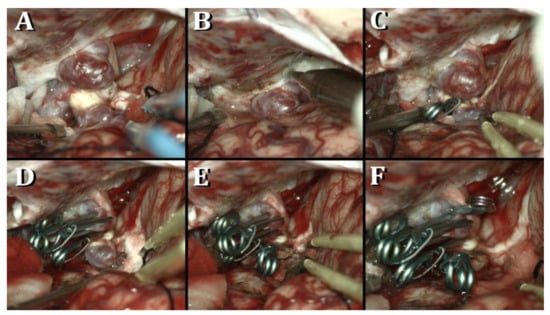

Microsurgical Clipping of Carotid-Ophthalmic Tandem Aneurysms: Case Report and Surgical Nuances

Costa, M.; Baldoncini, M.; Tataryn, Z.L.; Demichelis, M.E.; Conde, A.; Purves, C.; Giotta Lucifero, A.; Hernesniemi, J.; Luzzi, S. Microsurgical Clipping of Carotid-Ophthalmic Tandem Aneurysms: Case Report and Surgical Nuances. Medicina 2021, 57, 731. https://doi.org/10.3390/medicina57070731